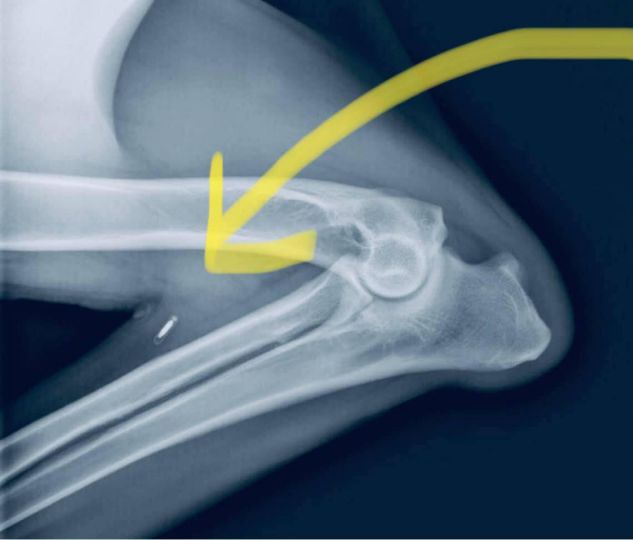

Ceci est une radio de la patte avant pliée d'un chien. Tu vois cette petite spécificité blanche ? C'est une micropuce ! Il a migré vers le bas de la jambe... loin de là où il a été inséré, entre les épaules du chien. C'est en fait assez commun...

Lorsque les animaux de compagnie perdus sont scannés, tout le corps DEVRAIT être scanné pour attraper ceux qui ont migré. Mais, en tant que propriétaire, C'EST VOTRE RESPONSABILITÉ À L'EXAMEN ANNUEL Vétérinaire, de demander un scan rapide pour vous assurer que : (1) la puce fonctionne toujours, (2) l'emplacement de la puce est bon, et (3) que les informations de la puce sont correctes.

Rappelez-vous que les micropuces sauvent des vies et réunissent les familles avec leur animal de compagnie Faites-le vérifier régulièrement !